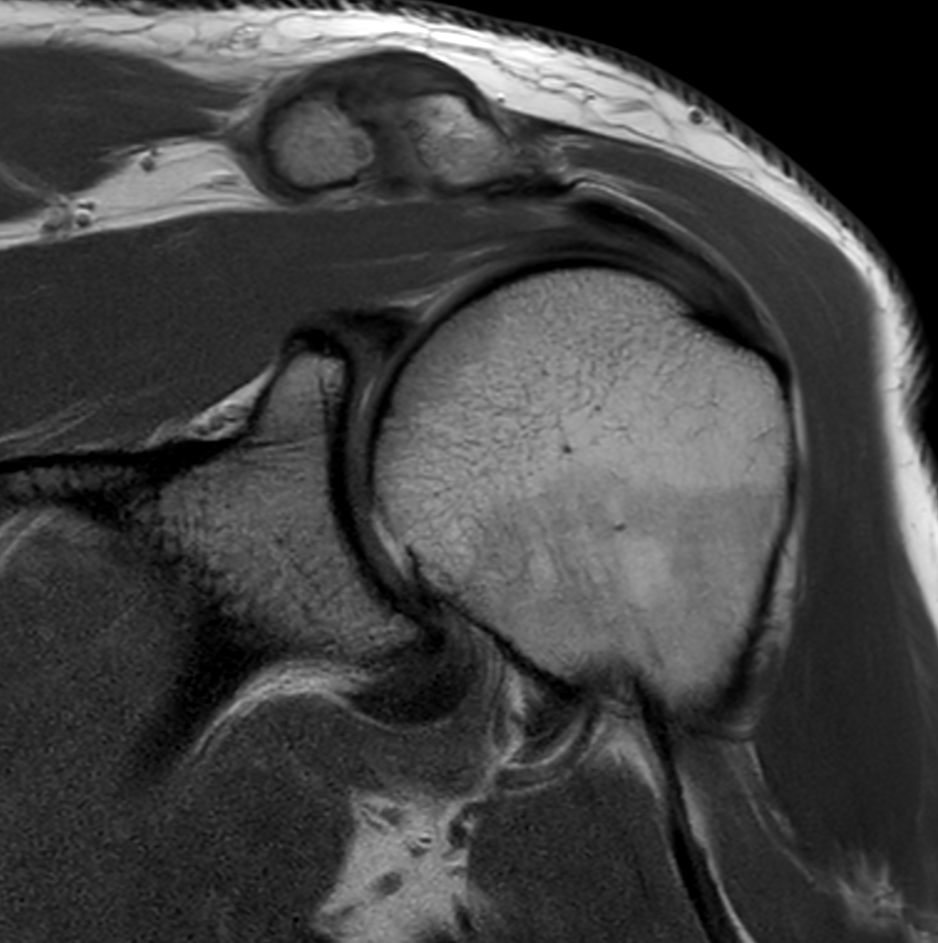

Shoulder with the dS Shoulder 16ch coil

University of Vermont Medical Center, Burlington, USA